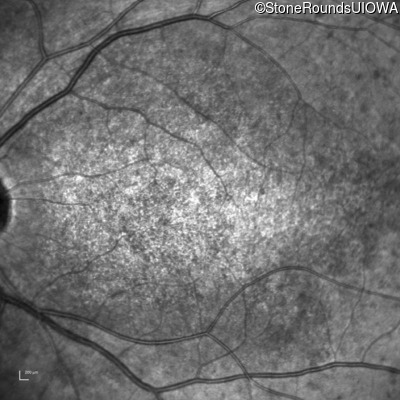

| Age at visit: 16 years |

| AR Stargardt Disease | ABCA4 | Ala1038Val GCC>GTC / Leu541Pro CTA>CCA | IVS36+3 del4tAAGT | AR |